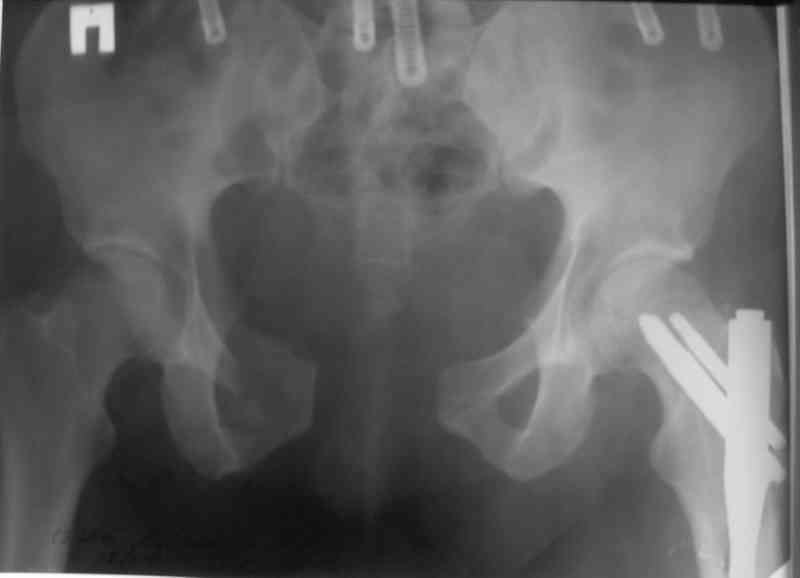

Пластина спереди (на лонные кости) открыто и каннюлированные винты с обеих сторон сзади - закрыто.

Предварительная репозиция может быть достигнута при помощи аппарата.